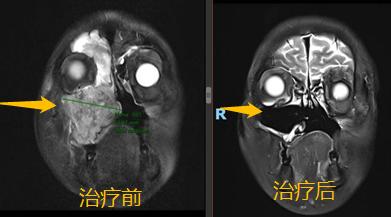

将病情和治疗新进展与患者及家属充分沟通后,医生和患者及家属达成了一致的想法,愿意先采用化疗联合免疫治疗的方法一试,其间密切跟踪右侧上颌窦肿瘤退缩情况。患者的充分信任和医生的努力换来了可喜的结果:一个疗程治疗后,患者的右半边头痛即得到了缓解,面部肿胀开始消退。两个疗程后行鼻腔鼻窦磁共振检查,肿瘤完全退缩。

继续乘胜追击!目前患者已完成6疗程的化疗和9疗程的PD-1抑制剂免疫治疗,正在继续免疫治疗维持中,患者鼻塞、牙痛、头痛等症状已完全缓解,生活基本正常。最新的磁共振显示,局部肿瘤已被完全控制!划重点!